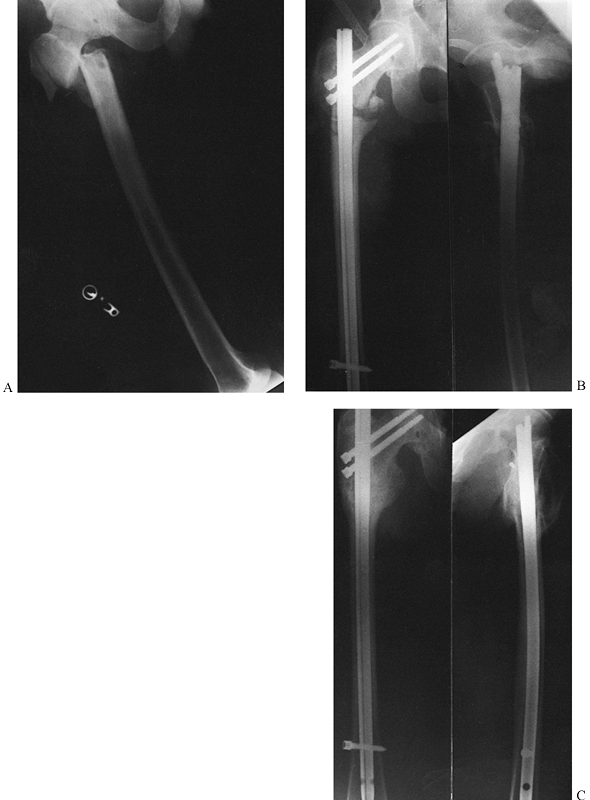

-

In community-based practices in North

America, the vast majority of displaced femoral neck fractures in

patients over 65 years of age are currently treated with

hemiarthroplasty (Fig. 19.7).

Figure 19.7. Hemiarthroplasty for a week-old Garden stage IV subcapital fracture of the femoral neck. A: AP radiograph showing a fully displaced fracture with some erosion of the head and femoral neck due to delay in fixation. B: Lateral radiograph. C: AP radiograph after cemented bipolar hemiarthroplasty. D: Lateral radiograph. -

or the newer bipolar prosthesis, including those that can be converted

to a total hip. These are available in both cemented and noncemented

versions (Fig. 19.7).